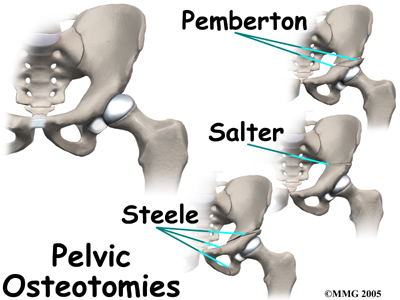

Surgical treatment for containment usually consists of procedures that realign the femur (thighbone), the acetabulum (hip socket), or both.

Realignment of the acetabulum is called a pelvic osteotomy. This procedure changes the angle of the acetabulum (socket) so that it better covers, or contains, the femoral head. To perform this procedure, an incision is made in the side of the buttock. The bone of the pelvis is cut and realigned in a new position. Large metal pins or screws are then inserted to hold the bones in the new position until the bone has healed. The pins usually must be removed once the bone has healed.

Osteotomy Types